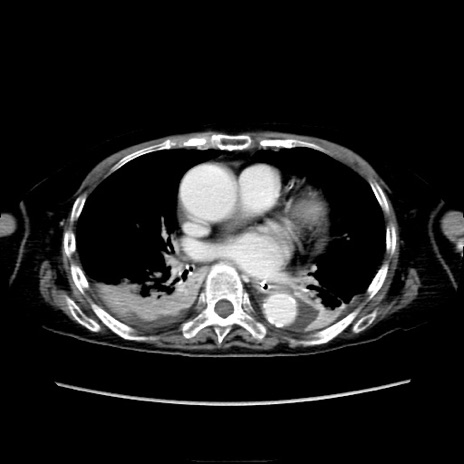

症例40(横断像)

横断像